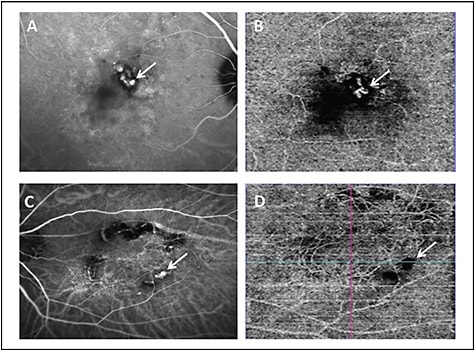

These disorders include pachychoroid pigment epitheliopathy (PPE), central serous chorioretinopathy (CSCR), polypoidal choroidal vasculopathy (PCV), and pachychoroid neovasculopathy (PNV).26 Optical coherence tomography angiography can be helpful in the diagnosis of PNV as a form of type 1 CNVM in eyes with PPE.27 The gold standard test for diagnosis of PCV is ICGA. The sensitivity and specificity of OCTA compared to ICGA is less for identifying polyps. However, branching vascular network (BVN) are better identified on OCTA.28 Examples showing BVN and polyps in cases of PCV using ICGA and OCTA are shown in Figure 3.